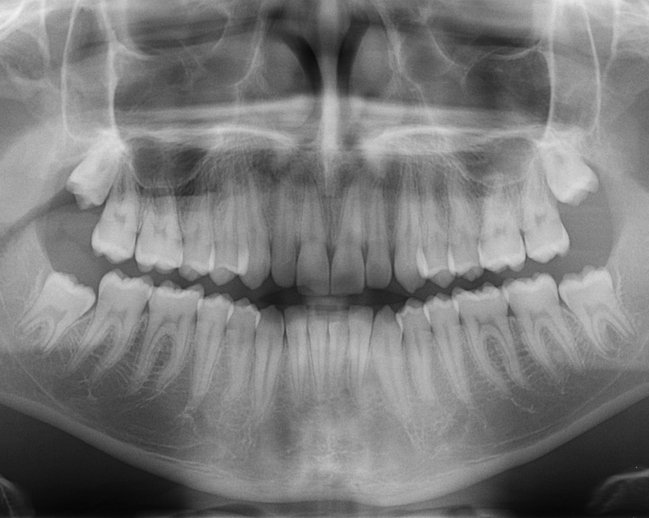

Panoramik Röntgen

Panoramik röntgen ile dişlerin tamamının görüntülenmesi sağlanır. Röntgende filmi ağzın dışına yerleştirilerek çekim gerçekleşir ve dişler ile çevre dokularla beraber tüm üst-alt çene ve çene eklemlerinin incelenmesi sağlanır. İmplantlar, gömülü dişler, kistler vb. işlemlerin uygulanabilmesi amacıyla kullanılan bir görüntüleme yöntemidir.